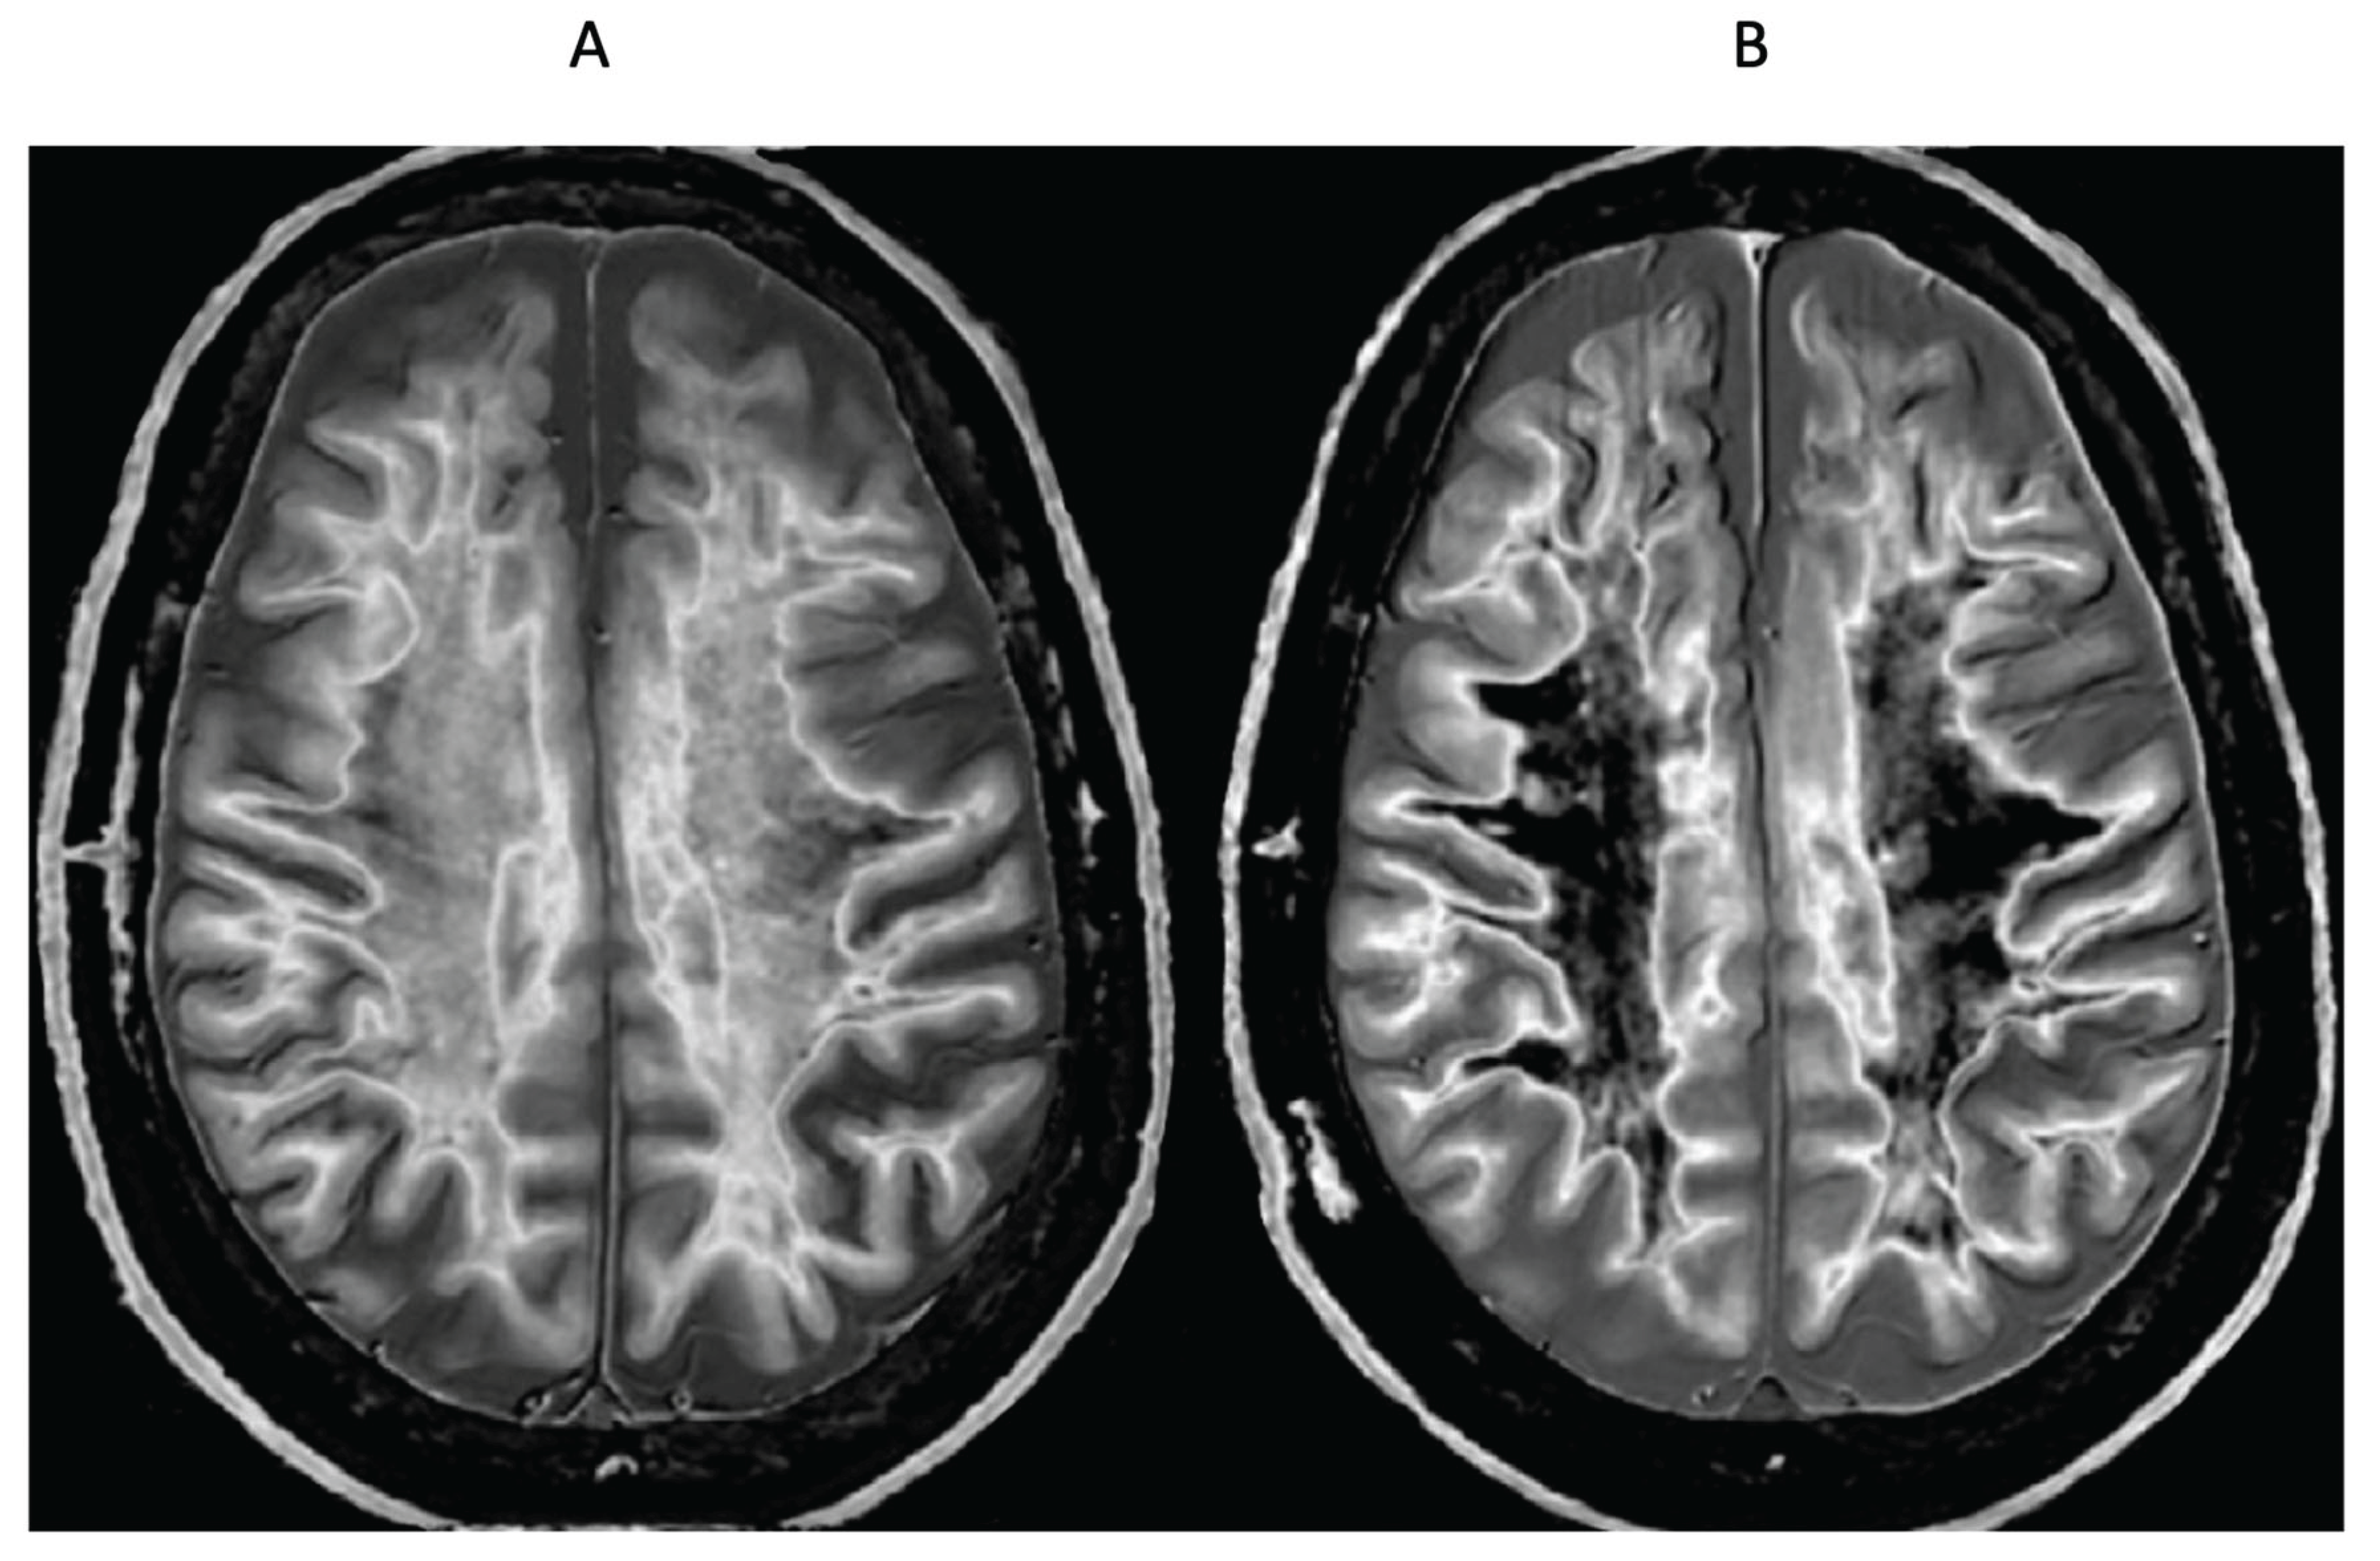

- Delayed Post-Hypoxic Leukoencephalopathy (Grinker’s Myelinopathy)

- Parkinson’s Disease

- Condron, P.; Cornfeld, D.M.; Scadeng, M.; Melzer, T.R.; Newburn, G.; Bydder, M.; Kwon, E.E.; McGeown, J.P.; Handsfield, G.G.; Emsden, T.; et al. Ultra-High Contrast MRI: The Whiteout Sign Shown with Divided Subtracted Inversion Recovery (dSIR) Sequences in Post-Insult Leukoencephalopathy Syndromes (PILS). Tomography 2024, 10, 983–1013. [Google Scholar] [CrossRef] [PubMed]

- Newburn G, Condron P, Kwon EE, et al Diagnosis of delayed post-hypoxic leukoencephalopathy (Grinker’s myelinopathy) with MRI using divided subtracted inversion recovery (dSIR) sequences: time for reappraisal of the syndrome? Diagnostics 2024, 14, 418. [CrossRef]